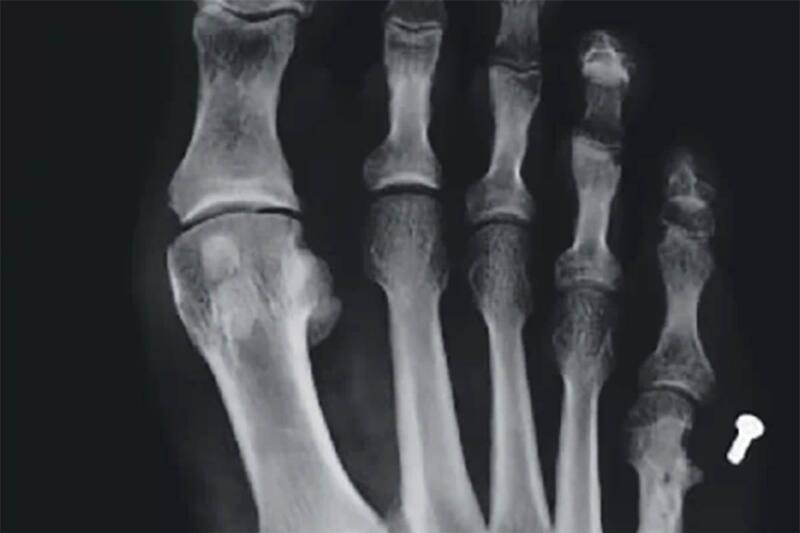

Pasaron tres años y Guerrero fue de nuevo al médico porque le dolía otra vez el pie. El mismo doctor que lo operó le hizo una radiografía y notó que un tornillo se había desprendido. Según el galeno, esto podía pasar. Además, con el hueso completamente regenerado, ya era tiempo de sacar las placas y los tornillos en otra operación.

De esa segunda cirugía, el paciente cuenta que no logró recuperarse completamente. De hecho, no podía ni usar zapatillas normales, razón que lo llevó a consultar a otro médico. El hallazgo fue tremendo, el tornillo suelto seguía dentro de su pie.

Por no tener dinero para una tercera operación, estuvo tres años con dolor y sin poder caminar bien. Esto lo llevó a demandar al primer médico por negligencia. El error, según la instancia judicial que dictó el fallo, es que este no realizó una radiografía de control tras la segunda operación.

En el mismo tribunal, el médico explicó que él había “contado los tornillos” y que “no le constaba que había quedado uno en el interior (del pie)”.